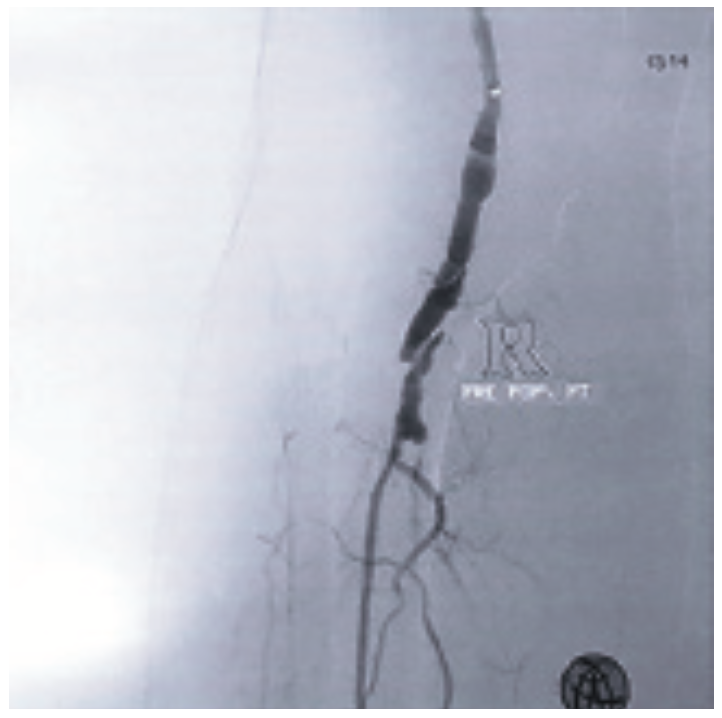

This gentleman was subsequently referred to our OBL, and in August 2017, underwent a diagnostic angiogram of the right leg via a contralateral approach, which showed a large, eccentric linear dissection in the right P2 segment of the popliteal artery. There was single-vessel runoff to the foot via the right peroneal vessel, and the right anterior tibial (AT) was completely occluded, with no demonstrable nub.

The small nub of the right posterior tibial (PT) extended only about 2-3 mm, with no runoff to the right foot. We initially attempted to cross the eccentric dissection at the level of the right popliteal artery to get into the true lumen using multiple wires, but were unsuccessful. Every wire we attempted went into the flap of the dissection. At that point, we elected to use the Destruction of Arteriosclerotic Blockages by laser Radiation Ablation (DABRA) catheter and laser (Ra Medical), a non-thermal excimer laser system that received FDA market clearance in May 2017, to ablate near the severely stenotic area in the P2 section of the popliteal artery. We made three passes with the DABRA, with the help of a 6 French (Fr) x 90 cm supportive sheath. The DABRA made the turn and stayed in the true lumen, making a small channel by ablating the plaque very close to the dissection without causing further dissection, in what is described as micro-plaque ablation. DABRA allowed us to perform accurate, precise plaque ablation around the dissection and resulted in a clear, smooth channel for laminar flow within the true lumen, enabling the 0.14-inch Glide wire (Terumo) to easily cross the critical stenosis at the level of the dissection. With a support catheter, the totally occluded PT was easily crossed and the wire was placed into the distal PT, followed by a 3.0 mm x 200 mm-long balloon inflated for three minutes. A 3.5 mm x 40 mm balloon was used to treat the ostium of the PT and the popliteal artery at 10 to 12 atmospheres for three minutes. Subsequently, the support catheter and wire were removed, and a small amount of contrast was injected, confirming we were in the true lumen in the distal PT.